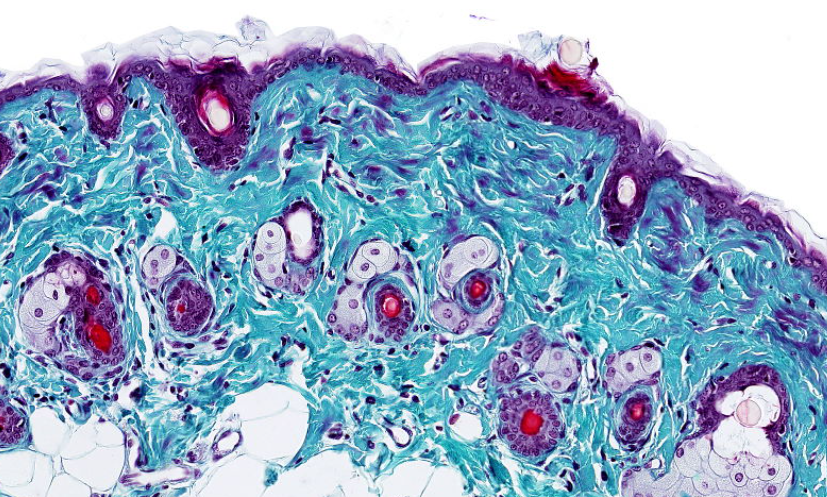

ÓRGANOS OTOLÍTICOS

Mácula del utrículo: detecta movimientos horizontales.

Mácula del sáculo: detecta movimientos verticales.

Mácula, HyE.